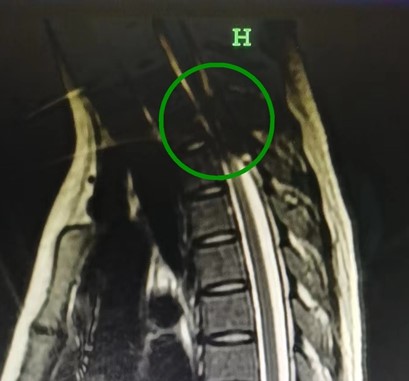

神经外科主任黄其林教授了解情况后,深感不妙,“患者病程短、病情进展快,已经出现严重的脊髓压迫症状,外院磁共振提示病灶在胸2-3椎体平面椎管内;一旦病灶继续向上发展,极有可能引发高位截瘫、甚至出现呼吸困难,要尽快手术!”

胸部增强核磁共振平扫报告提示:小秋胸2-3水平硬膜外占位性病变,考虑急性期硬膜外血肿或硬膜外血管畸形伴出血。

对此,黄其林教授马上组织科室会诊,诊断患者为椎管内出血,因出血量大,脊髓急性压迫,导致双下肢肌力减退、大小便功能障碍等,有急诊手术治疗指征。